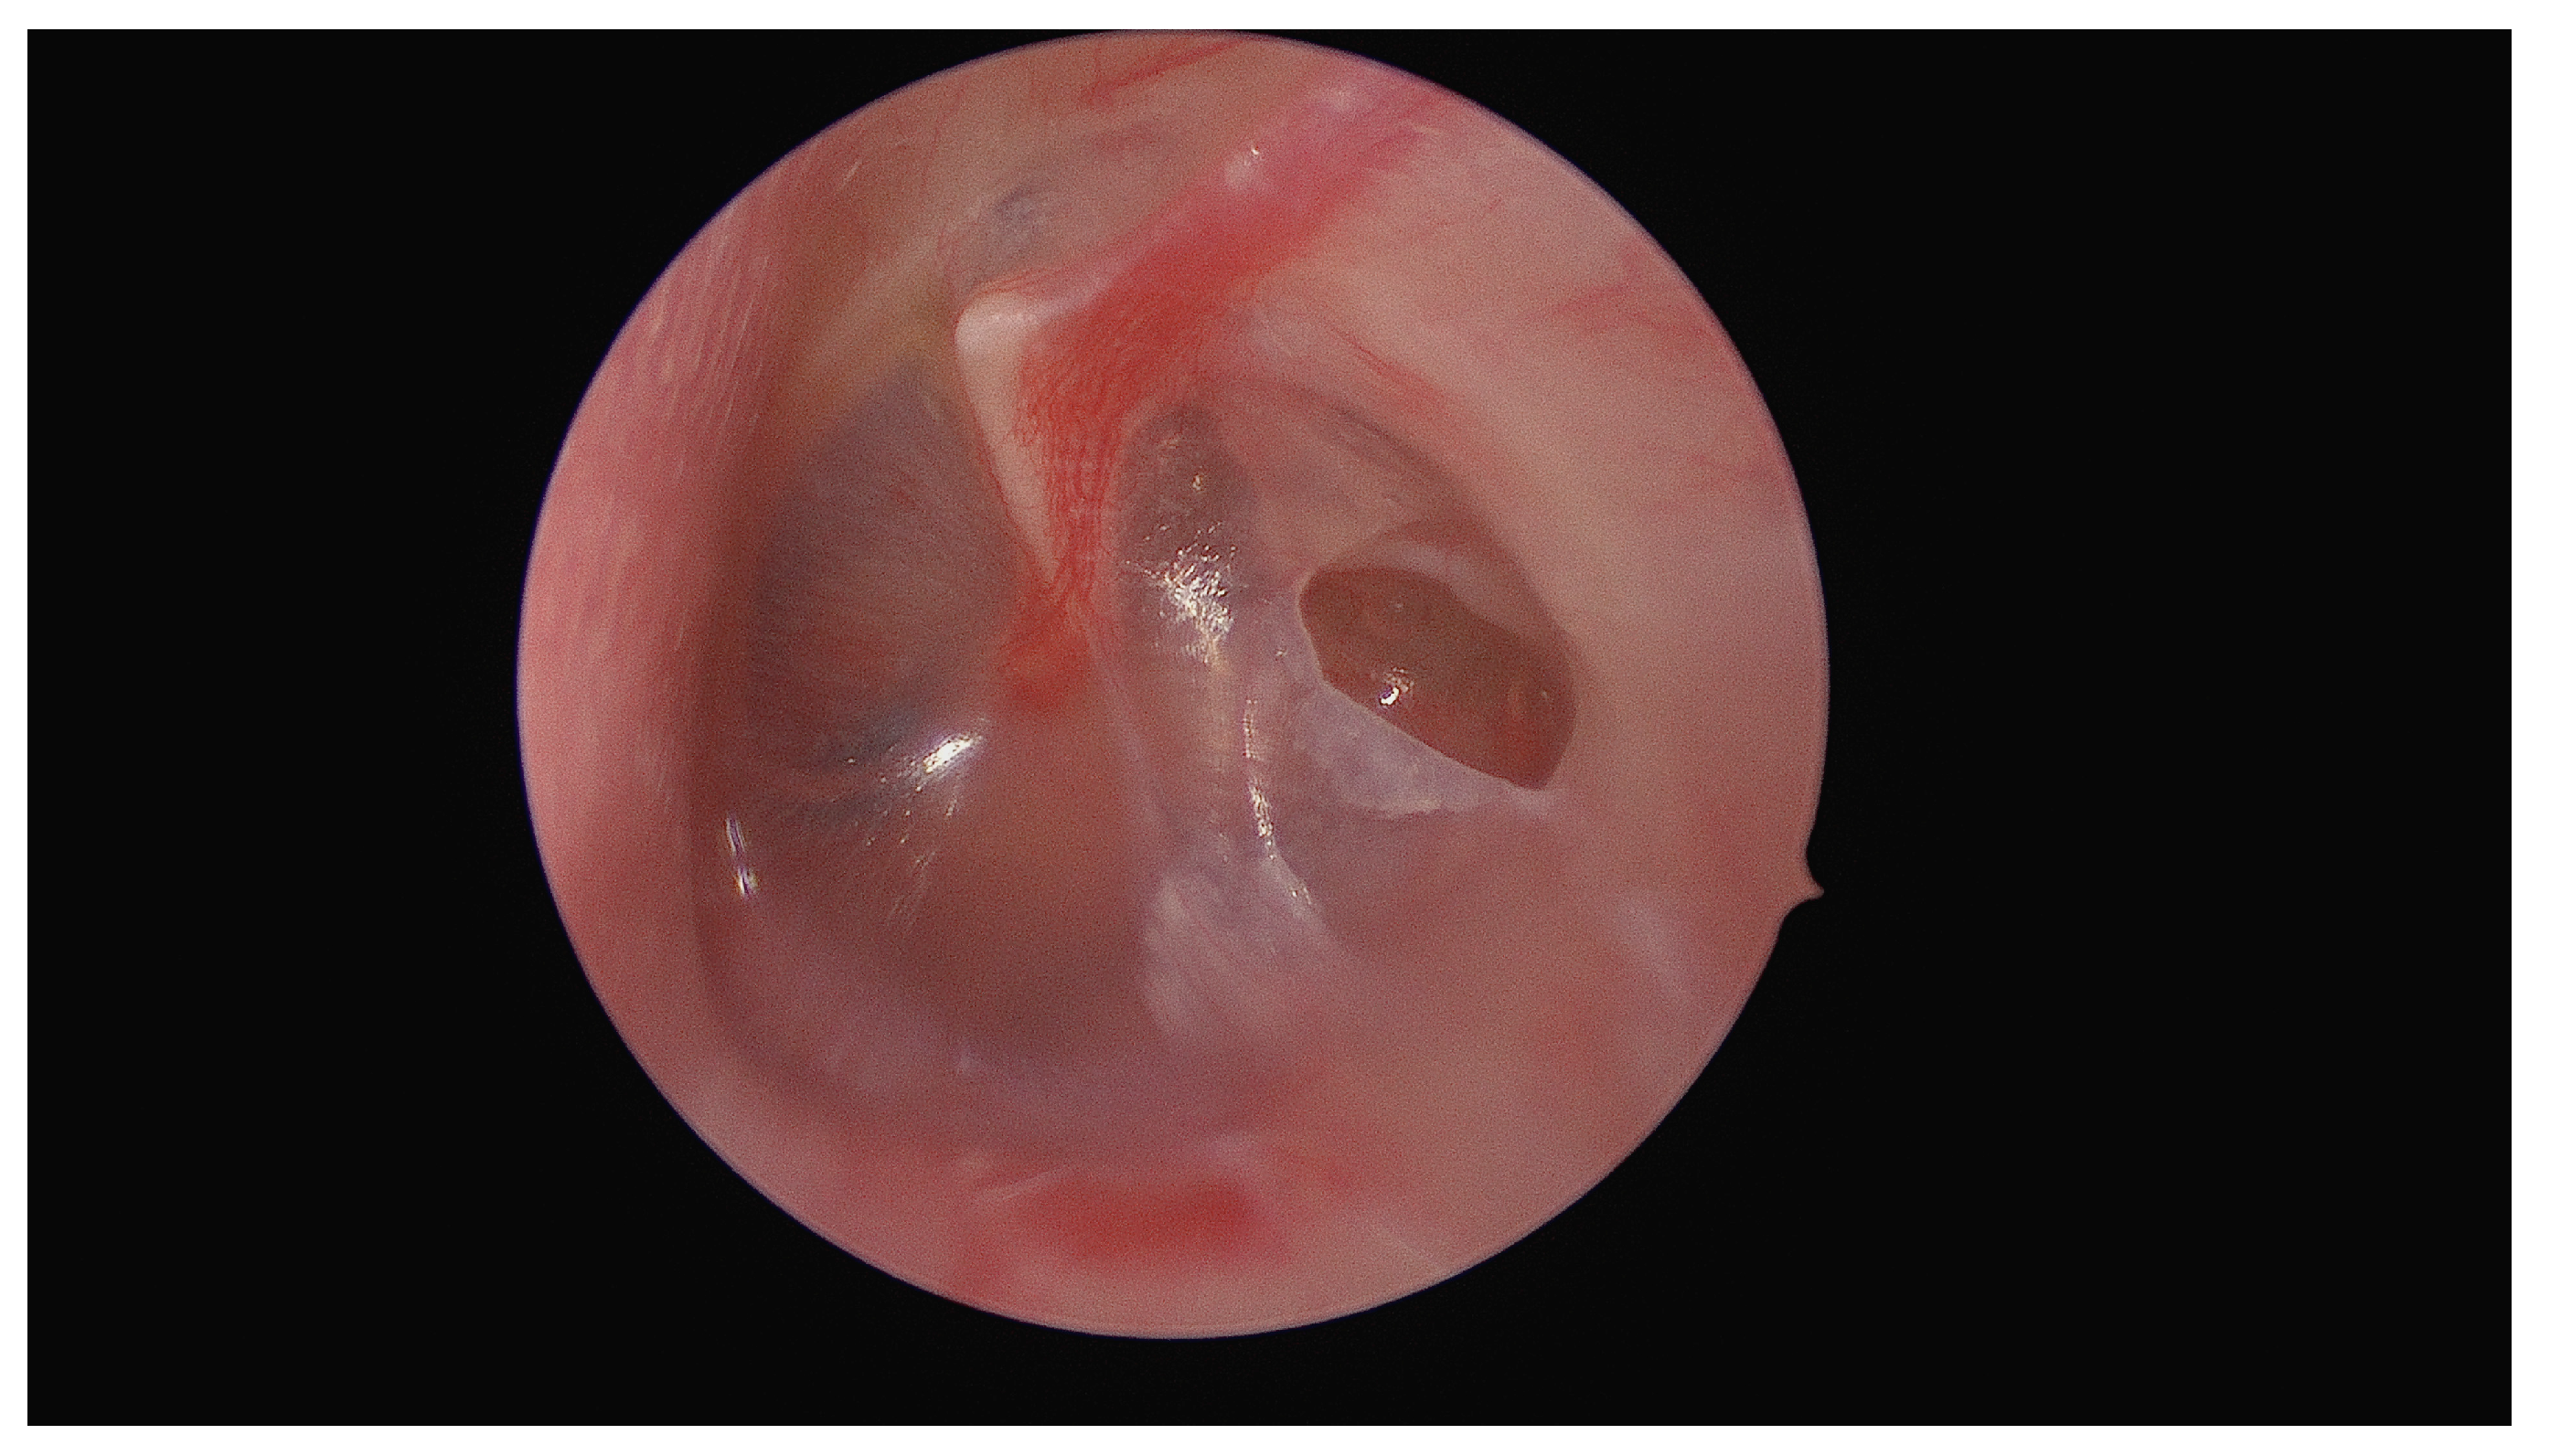

Unusual Foreign Body in the Middle Ear: Surgical Removal of a Live Ant Entering the Tympanic Cavity Through an Ear Drum Perforation